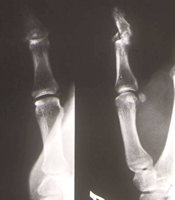

Mittelgliedköpfchenfraktur des kleinen Fingers - Ergebnis nach geschlossener Reposition

Diese schwer zu stabilisierende Köpfchenfraktur läßt sich ohne großen Aufwand mit dem Minifixateur stabilisieren. Die Reposition ist einfach.